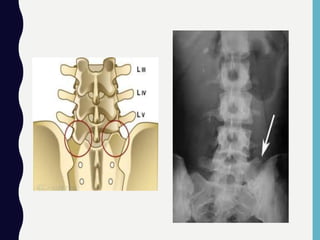

Gambaran Radiologi

• Terplesetnya vertebra

paling baik diperlihatkan

pada proyeksi lateral dari

tulang belakang lumbal

dan mungkin ditemukan

rongga diskus yang

hilang.

• Paling sering terjadi

setinggi L4/L5 dan L5/S1.

CT/MRI dapat menilai dan

adanya penyempitan

kanal tulang.